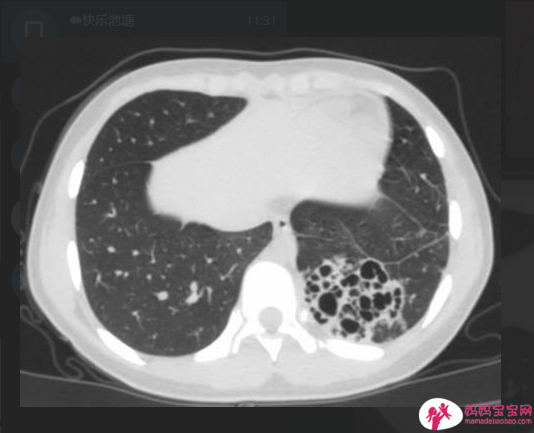

肺部X光是诊断新生儿的呼吸阵喘(TTN)必需的检查。肺部X光可看到肺部过度扩张,肺门边肺纹明显,轻微心脏肥大,小肺裂处有积液(fluid in minor fissure)且没有其他肺部感染病灶。在确诊新生儿呼吸阵喘(TTN)前,必须先排除其他疾病的可能:如新生儿呼吸窘迫症、新生儿败血病、新生儿肺炎、胎便吸入、先天性心脏病或气胸……等。

小于34周出生新生儿或因母体内科疾病,如:妊娠糖尿病延迟胎儿肺部成熟,可能要考虑婴儿呼吸窘迫症。这类新生儿出生后的呼吸窘迫状况会持续恶化,肺部X光呈现网状颗粒影像(reticulogranular pattern)、气管空气影像(air bronchogram)和塌陷未扩张的肺叶。若婴儿是足月或过熟,可能进一部考虑有胎便或羊水吸入。